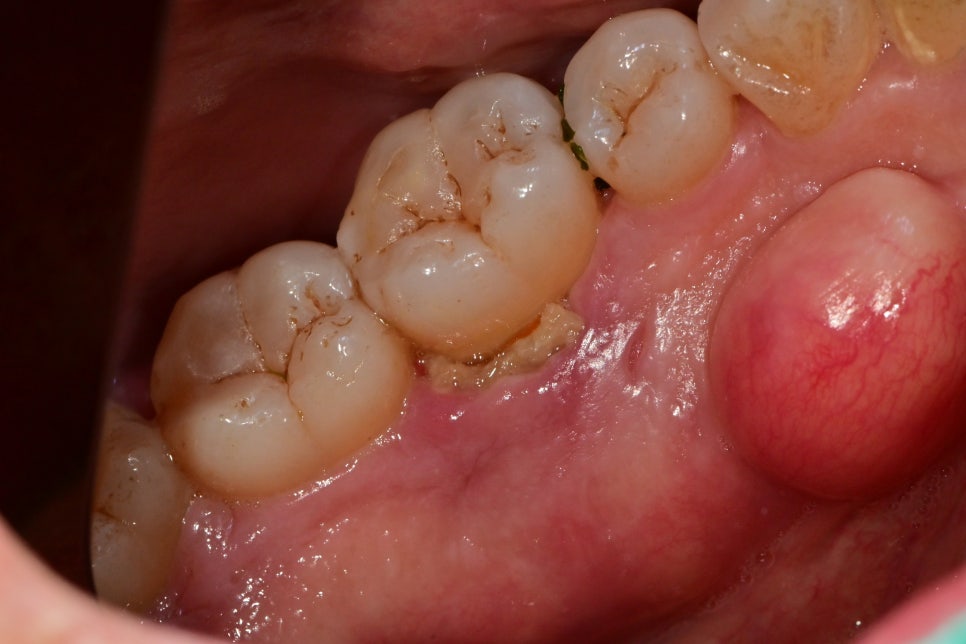

치주치료 완료 후 한 달 뒤에 동일 부위가 불편하셔서 내원하셨습니다.

헐어있는 잇몸과 주변 잇몸의 부종은 많이 가라앉아 정상적인 핑크색을 띠는 잇몸이 되어있지만

치조골이 파괴되어 생긴 깊은 포켓공간의 잇몸은 약하기 때문에

딱딱한 음식물 같은 것들이 잇몸에 잘 끼게 되어 불편감을 야기할 수 있습니다.

특히 이 환자분께서는

바깥쪽이 아닌 혀가 맞닿는 안쪽의 치조골에 치주염이 생긴 케이스로

음식물이 끼더라도 관리하기 어려운 부위기 때문에

자주 내원하셔서 저희와 같이 관리도 하고 치아 상태를 지속적으로 체크할 필요가 있습니다.